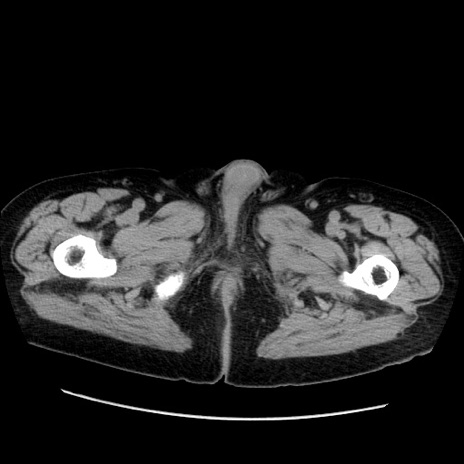

冠状断像

症例21(横断像)

【症例】70歳代男性

【現病歴】肝硬変・肝細胞癌にてかかりつけの方。約9時間前に食後より腹痛出現。症状が徐々に増悪し、嘔吐出現したため来院。

【既往歴】肝硬変、肝細胞癌(RFA、TACE後)